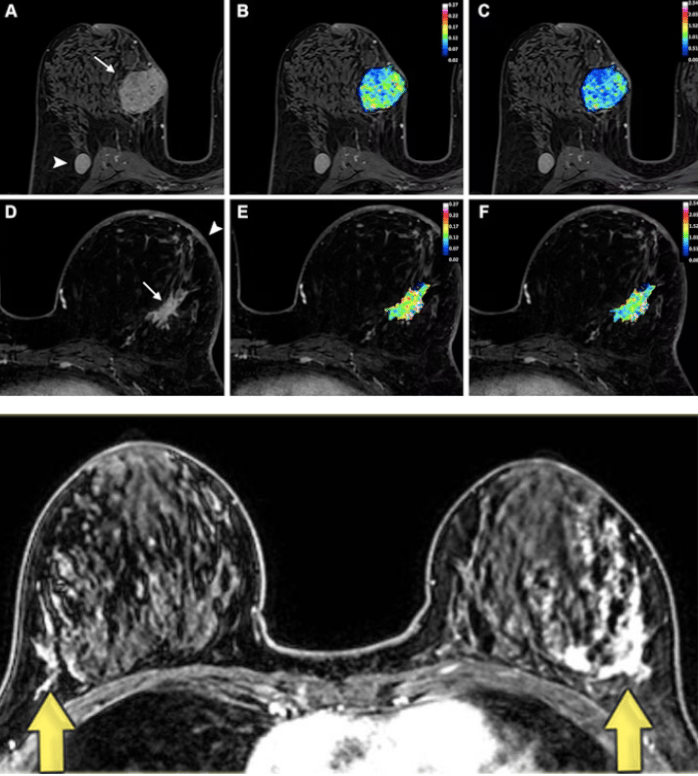

Breast Magnetic Resonance Imaging (MRI) uses powerful magnetic fields and radio waves to generate detailed, cross-sectional images of the breast.

Pros:

Radiation-free.

Effective for dense breasts.

Comfortable. Since there’s no compression involved, it’s a pain-free option.

Provides clearest pictures of the breast.

Can detect breast calcifications.

Cons:

May require a gadolinium-based contrast injection into a vein in the arm.

This contrast dye helps highlight breast tissue during MRI scans, but small amounts of gadolinium can remain in the body, accumulating in the brain and bones over time, especially with repeated imaging. It’s best to ask whether contrast is truly necessary or if a non-contrast MRI can provide similar information.Takes more time than other screening methods.

Can be expensive.

Can produce false positives.